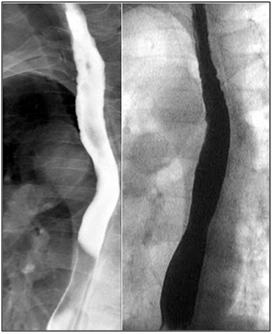

A 46 year-old male with end stage renal disease underwent deceased donor kidney transplant followed by immunosuppression with MMF, tacrolimus, and prednisone. Shortly after transplantation, he noted new solid food intermittent dysphagia with slow progression over 6 months. He was later hospitalized with progressive worsening of nausea, vomiting and dysphagia. Esophagogastroduodenoscopy (EGD) showed LA Class D esophagitis about 10 cm above the gastro-esophageal junction with a stenosisat 30cm from the incisors. Biopsies showed acute and chronic inflammation without increased eosinophils or evidence of Barrett’s mucosa. Stains for fungi, cytomegalovirus (CMV) and herpesvirus (HSV) were negative. He was treated with esomeprazole 40mg twice a day but was re-hospitalized one month later with persistent symptoms. A repeat EGD demonstrated once again LA Class D esophagitis with worsening stricture in the proximal part of the lower third of the esophagus along with candida plaques. Biopsies revealed severe esophagitis without CMV/HSV (Figure 1). The stricture was dilated up to 44 Fusing Maloney dilators and fluconazole and nystatin were added to his proton pump inhibitor (PPI).

Figure 1 20x (left) and 40x (right) views of desquamated squamous epithelium with associated acute fibrino-inflammatory infiltrates consisting predominantly of neutrophils with background reactive cytologic changes.